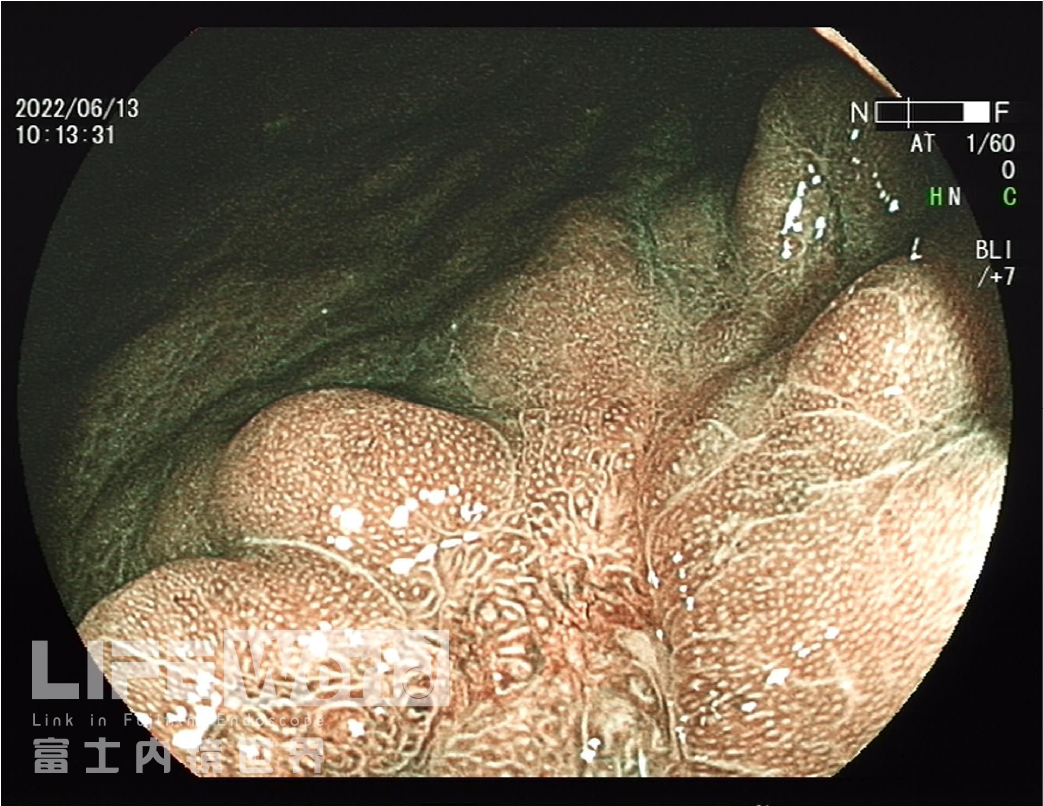

BLI模式低倍放大观察,可清晰的勾勒出病变的范围,病变的口侧端表面微结构的异型性明显,考虑为癌灶,病变的肛侧端异型性不明显,考虑为上皮内瘤变。

对考虑为癌灶的区域进行中倍放大观察:IMSP(+), IMVP(+)。